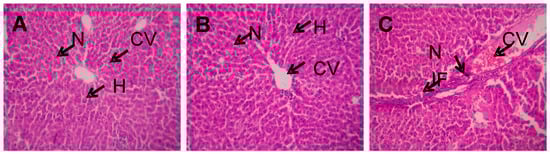

4.3. Histopathology Analysis